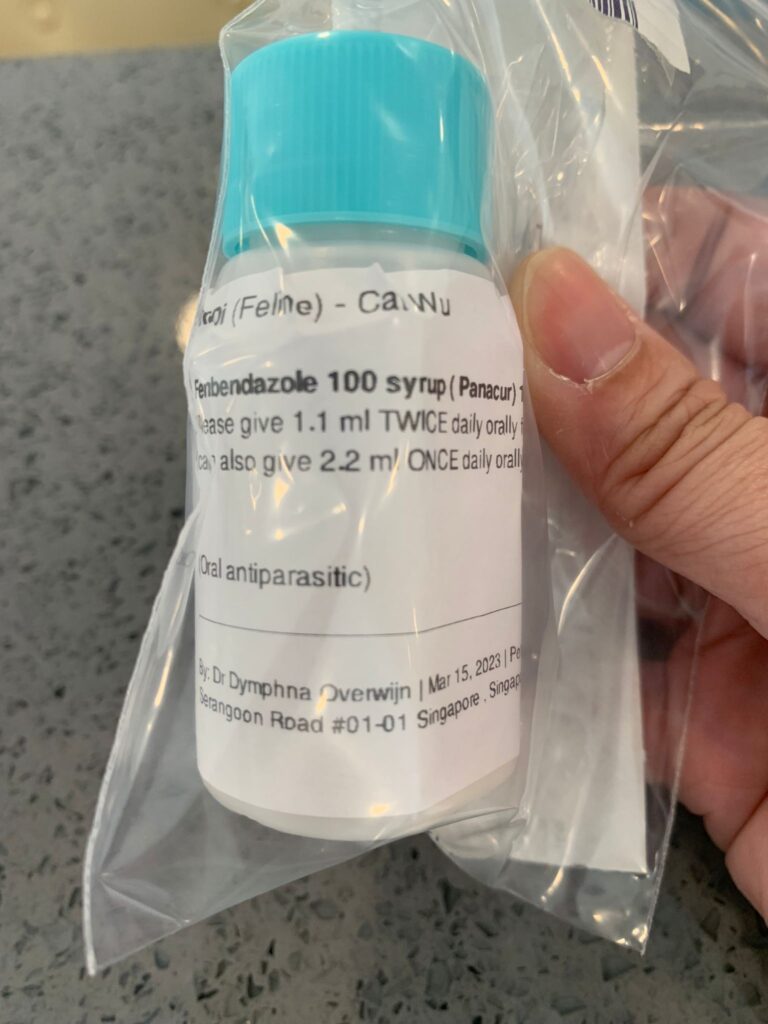

Morning; 4.32kg – gain 150g. Whole stomach like hard hard like that. Manage to give Sam e again. Today last day of fenbendazole. Subcut and give meds.

Night: given didi usual meds, fenbendazole surprisingly he didn’t puke as much as other cats. Pancur to feed 4 more days.

Tonight maybe I try giving deworming